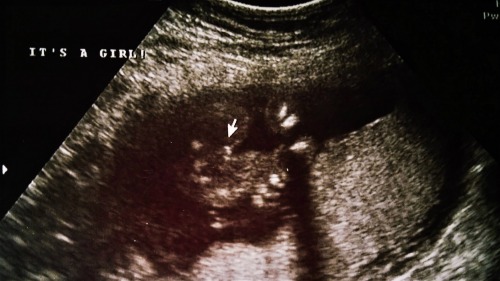

I really want a girl and was told 100% girl at my 18 week ultrasound, but I'm kind of in disbelief and keep studying the picture to make sure it is indeed a little girl. It looks like it could be small boy parts that the legs squished together. :/ Is it just my imagination? Does this really look like a girl?

Attachment 21349